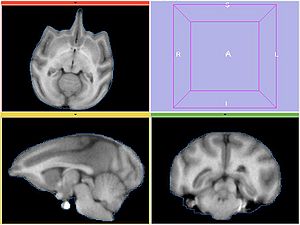

Experiment 4

Perform bias correction on the moving image prior to registration. Register MOVING_BIAS_CORRECTED/MOVING_ROI to FIXED2/FIXED_ROI. Initialize with INITIAL_TFM. No histogram matching applied.

REGISTERED4